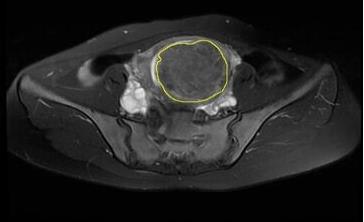

Objective To improve the accuracy of machine learning models for preoperative prediction of high-intensity focused ultrasound (HIFU) ablation efficacy for uterine fibroids by correcting class imbalance in small sample datasets using undersampling methods. Methods Clinical and imaging data were collected from 140 patients with uterine fibroids undergoing HIFU treatment at Foshan Women and Children Hospital, including 104 with high ablation rates and 36 with low ablation rates. Radiomic features were extracted from MRI T2-weighted images (T2WI) of the patients, and machine learning models were constructed to predict HIFU treatment outcomes. Four machine learning algorithms, including k-Nearest Neighbors (KNN), Random Forest (RF), Support Vector Machine (SVM), and Multilayer Perceptron (MLP), were coupled with 7 undersampling methods, namely Random Undersampling (RUS), Repeated Edited Nearest Neighbors (RENN), All k-Nearest Neighbors (AllKNN), Neighborhood Cleaning Rule-3 (NM), Condensed Nearest Neighbor (CNN), Neighborhood Cleaning Rule (NCR), and Instance Hardness Threshold (IHT), for handling class imbalance in the datasets. The 28 prediction models were evaluated using 5-fold cross-validation for areas under the receiver operating characteristic curve (AUC), accuracy, recall, and specificity. Results The best combinations of undersampling methods and machine learning models CNN-RF, NM-SVM, CNN-KNN, and NM-MLP had AUCs of 0.772 (95% CI: 0.566-0.942), 0.797 (95% CI: 0.600-0.950), 0.822 (95% CI: 0.635-0.964), and 0.822 (95% CI: 0.632-0.960), respectively. The AUCs of the machine learning models significantly increased after coupling with undersampling methods, with the MLP model showing the most pronounced improvement. The recall rates of the 4 combined models also improved significantly (by 0.389 for CNN-RF, 0.836 for NM-SVM, 0.532 for CNN-KNN, and 0.372 for NM-MLP). Conclusion The use of undersampling methods can effectively correct class imbalance in small sample datasets to improve the accuracy of machine learning models for predicting the efficacy of HIFU ablation for uterine fibroids.